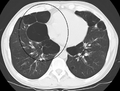

A chest X-ray and complete blood count may be useful to exclude other conditions at the time of diagnosis.[61] Characteristic signs on X-ray are overexpanded lungs, a flattened diaphragm, increased retrosternal airspace, and bullae while it can help exclude other lung diseases, such as pneumonia, pulmonary edema or a pneumothorax.[62] A high-resolution computed tomography scan of the chest may show the distribution of emphysema throughout the lungs and can also be useful to exclude other lung diseases.[15] Unless surgery is planned, however, this rarely affects management.[15] An analysis of arterial blood is used to determine the need for oxygen; this is recommended in those with an FEV1 less than 35% predicted, those with a peripheral oxygen saturation of less than 92% and those with symptoms of congestive heart failure.[14] In areas of the world where alpha-1 antitrypsin deficiency is common, people with COPD (particularly those below the age of 45 and with emphysema affecting the lower parts of the lungs) should be considered for testing.[14]

A severe case of bullous emphysema

Axial CT image of the lung of a person with end-stage bullous emphysema.